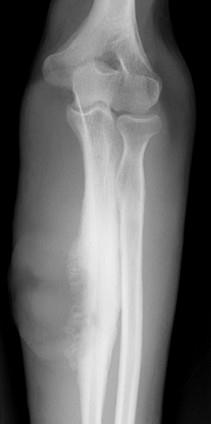

问题 女,35岁,有药物滥用史,右前臂疼痛、肿胀、溃疡,请结合图像,选出最可能的诊断 ( )

选项 A、骨结核 B、骨化性肌炎 C、成骨肉瘤 D、Ewing肉瘤 E、化脓性骨髓炎

答案 E